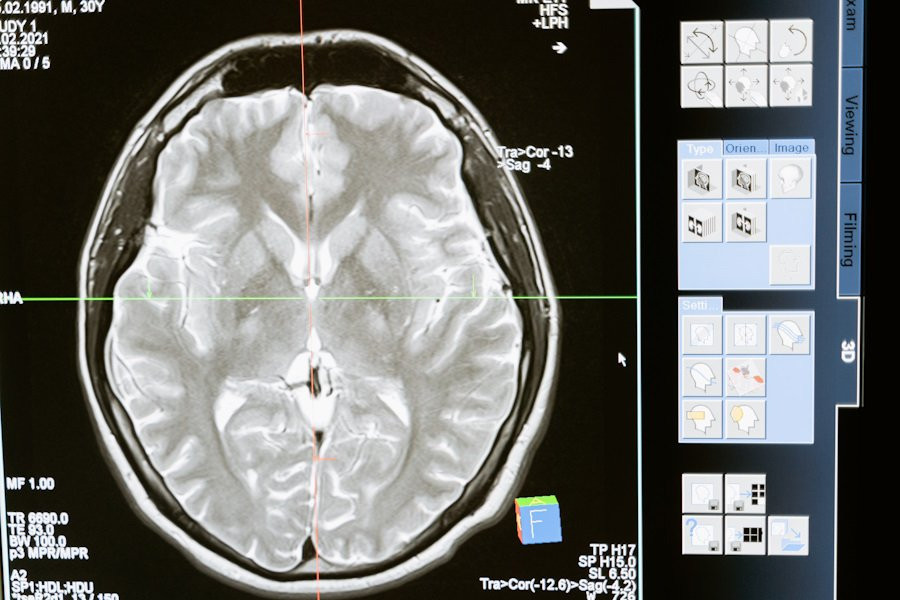

Исследователи University of Stanford (США) разработали модель ИИ (искусственного интеллекта), с достоверностью > 90% определяющую пол человека на основе МРТ его мозга. Этот прорыв бросает вызов давним спорам о существовании значительных половых различий в организации мозга, сообщает Neuroscience News (NN).

Модель искусственного интеллекта была сфокусирована на анализе динамических данных магнитно-резонансной томографии (МРТ), выявляя определенные сети мозга, такие как режим по умолчанию, полосатое тело и лимбические сети. Эти области оказались решающими для различения мужского и женского мозга.

В результате исследования было обнаружено, что способность модели ИИ различать снимки мозга мужчин и женщин с высокой точностью не только подчеркивает внутренние половые различия в организации мозга, но и предоставляет ценную информацию для понимания развития мозга и старения.

Ключевые сети мозга, выявленные этим исследованием, включают режим по умолчанию, полосатое тело и лимбическую сеть, которые играют важную роль в когнитивных функциях и поведении.